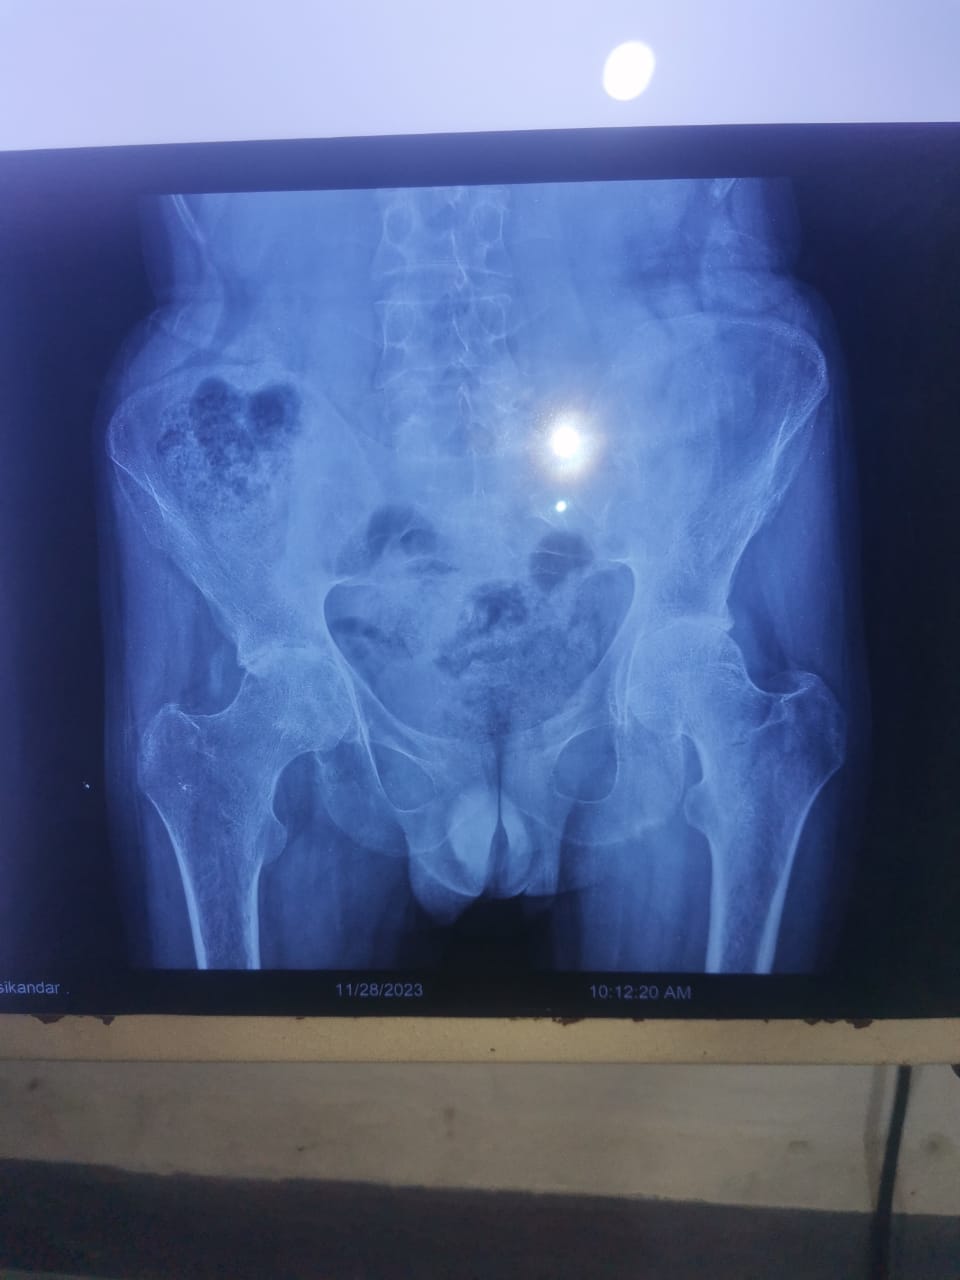

I have avascular necrosis from 1 year. I got some medicine treatment but nothing works. Now its feel worse day by day. X-rays shows that the condition of avn is reach to stage 3. I can't send x-ray because of my mobile camera result. What should i do?

Hello mam! Actually i want to know about surgery cost. Can you please give me idea about cost of total hip replacement? My x-ray is attached

Sir can you tell me about cost of surgery? My x-ray is attached

Sir i think i need new joint. You can check my x-ray. But i want to know about the cost of new hip. And what kind of hip is Good for me? My age is 27